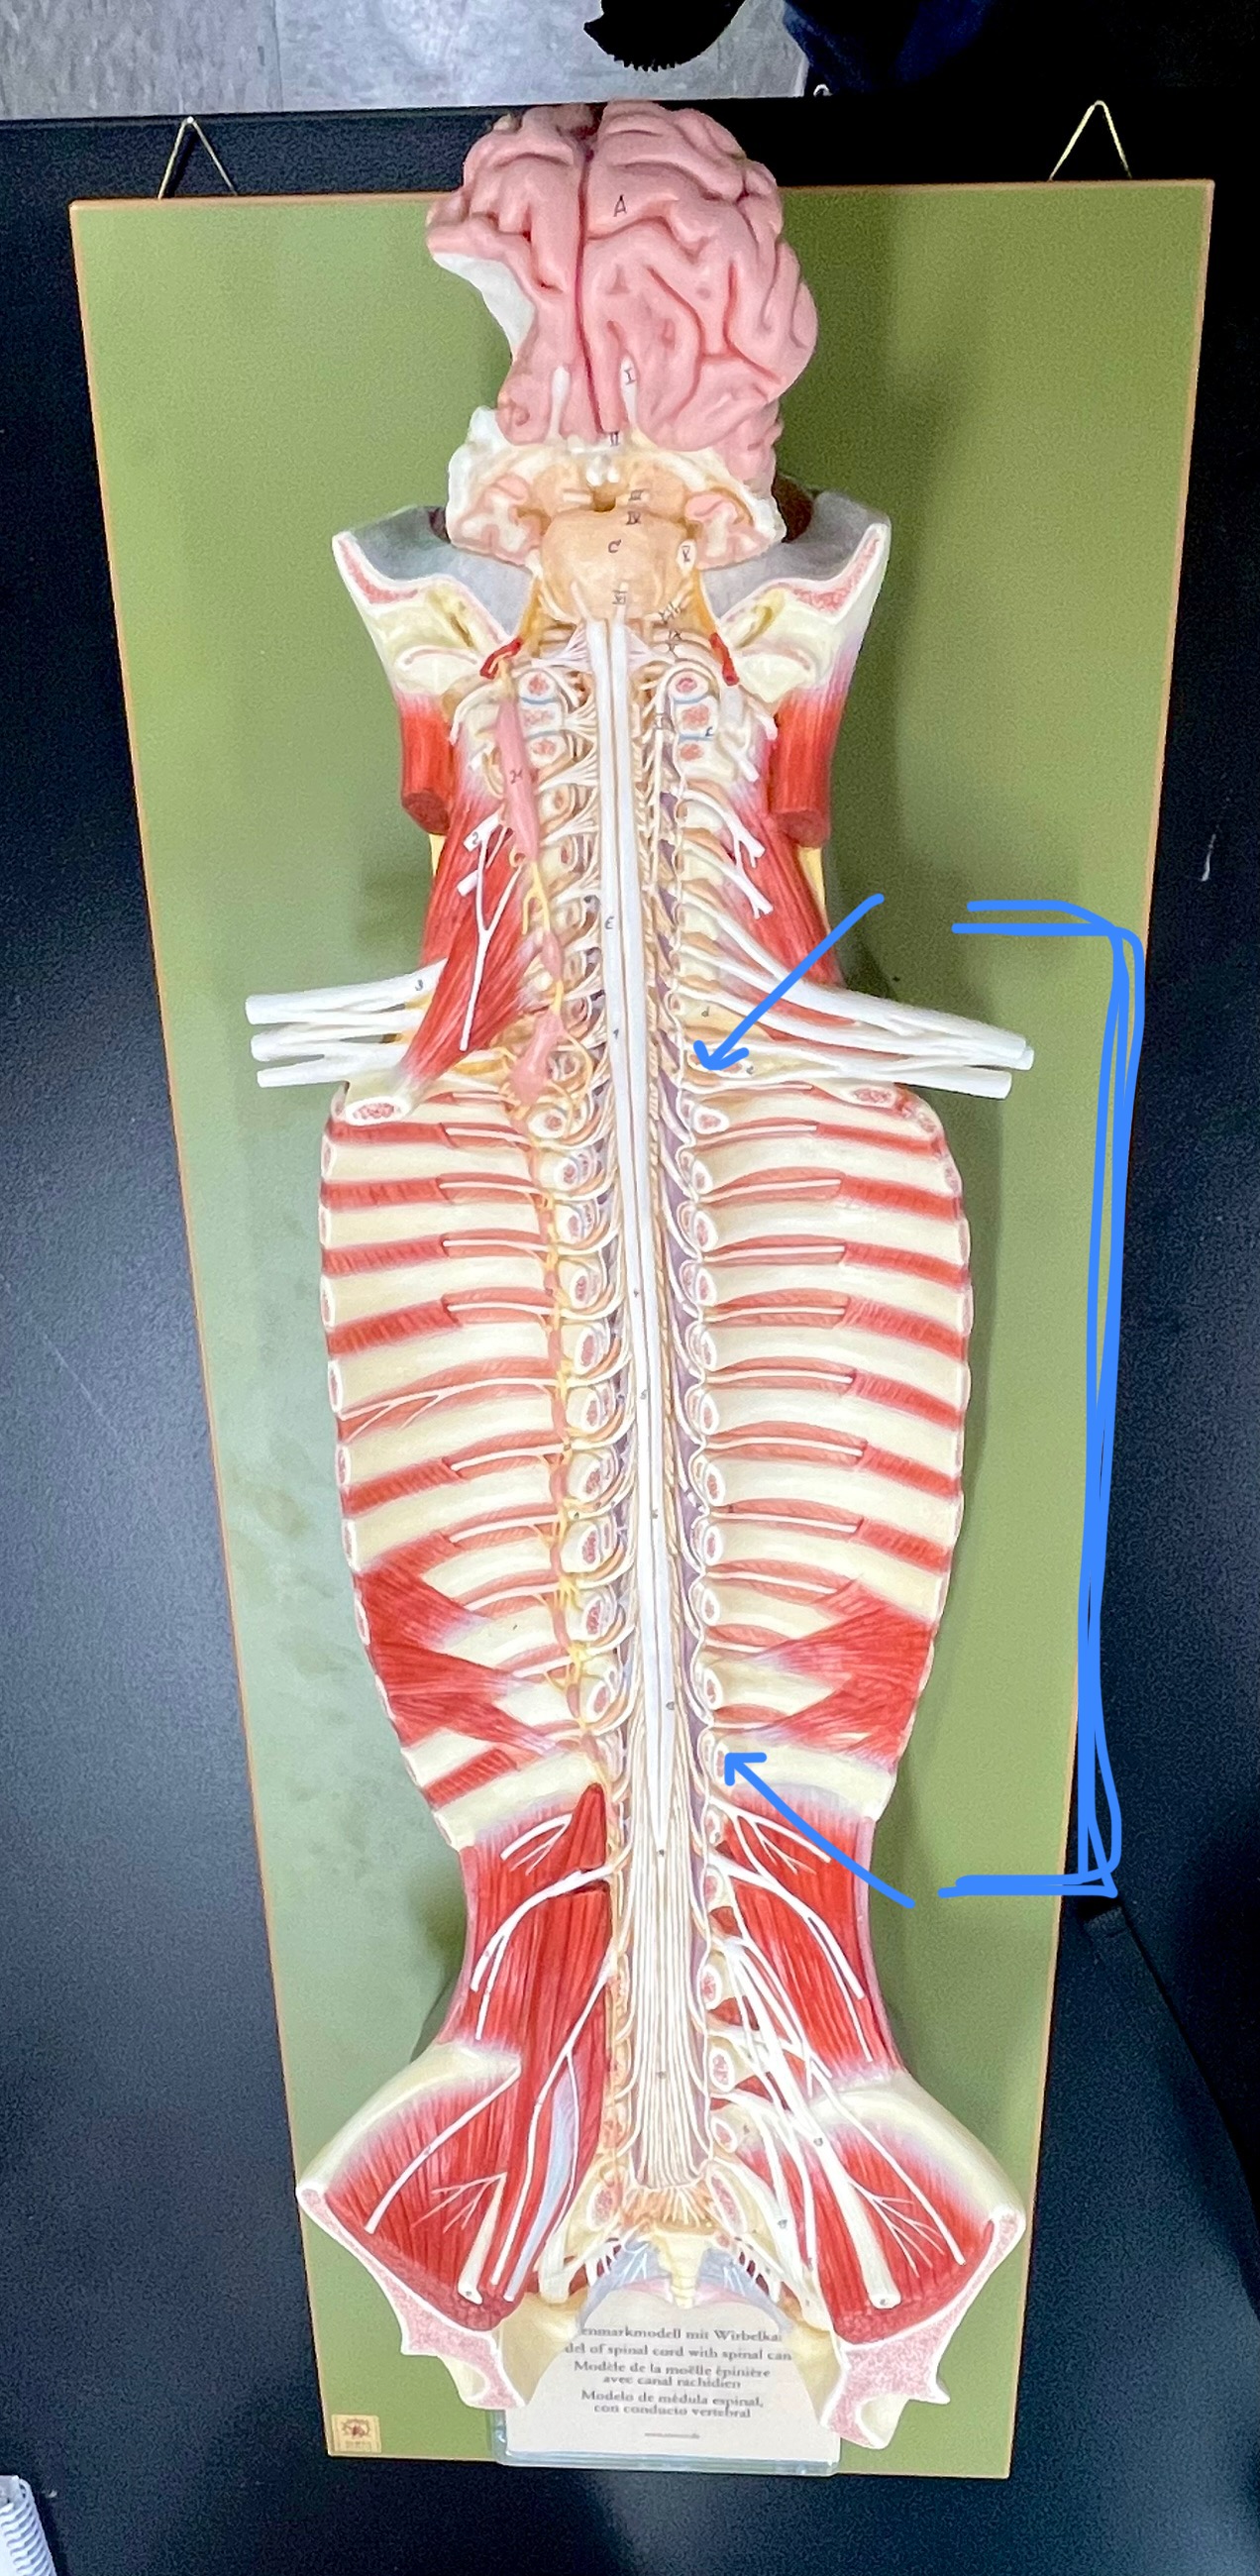

What type of spinal nerve is this? How many pairs?

cervical (8 pairs)

What type of spinal nerve is this? How many pairs?

thoracic (12 pairs)

What type of spinal nerve is this? How many pairs?

lumbar (5 pairs)

What type of spinal nerve is this? How many pairs?

sacral (5 pairs)

What type of spinal nerve is this? How many pairs? (not pictured)

coccygeal (1 pair)

cervical enlargement

cervical enlargement

thoracic segment

lumbar enlargement

lumbar enlargement

conus medullaris

conus medullaris

filum terminale

cauda equina

sympathetic chain ganglia

cervical plexus – phrenic nerve

cervical plexus – phrenic nerve

brachial plexus – ulnar nerve

brachial plexus – median nerve

brachial plexus – radial nerve

lumbar plexus – femoral nerve

lumbar plexus - femoral nerve

sacral plexus – sciatic nerve

sacral plexus – sciatic nerve